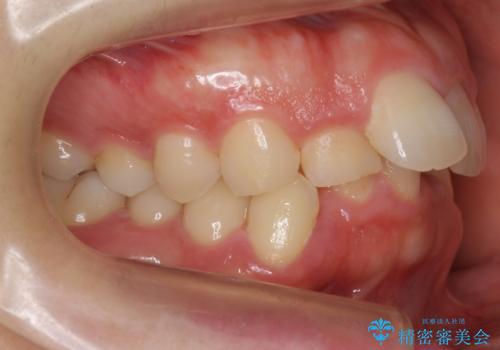

- 前歯のがたがたと出っ歯を主訴に来院。

CTを撮影したところ、臼歯部の頬側の骨の厚みが非常に大きく、通常では考えられない量の歯列の拡大が可能でした。

今回は健康を損なわずに非抜歯で治療が可能でしたが、

歯ぐきや骨の厚みが薄い他の患者さんでは難しいです。

左上5は180度捻転していましたので、そのまま並べています。

遠心移動などは行わず、IPRと拡大のみで治療を行いました。

一般的に非抜歯矯正を無理に行うと、口元がモッコリ出てしまうことがあります。しかし、今回は前歯を前に出さないような設定にしており、口元が出ることもありませんでした。